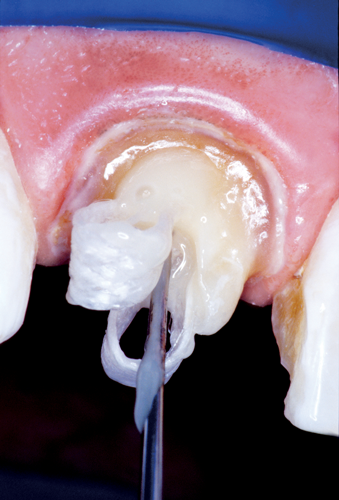

The traditional custom cast dowel core provides a better geometric adaptation to excessively flared or elliptical canals and almost always requires minimal removal of tooth structure.1 Custom cast posts and cores adapt well to extremely tapered canals or those with a noncircular cross section and/or irregular shape and roots with minimal remaining coronal tooth structure.22 Patterns for custom cast posts can be formed either directly in the mouth or indirectly in the laboratory. Regardless, this method requires two appointment visits and a laboratory fee. Also, because it is cast in an alloy with a modulus of elasticity that can be as high as 10 times greater than that of natural dentin,40 this possible incompatibility and rigidity can create stress concentrations in the less rigid root, resulting in post separation or failure.41,42 Additionally, the transmission of occlusal forces through the metal core can focus stresses at specific regions of the root, causing root fracture (Figure 3).40 Furthermore, upon esthetic consideration, the cast-metal post can result in discoloration and shadowing of the gingiva and the cervical aspect of the tooth (Figure 4).43

Fig 4. A maxillary right central incisor was restored with a cast-metal post, which can result in discoloration and shadowing of the gingiva and cervical aspect of the tooth. The incidental light was completely blocked by the metal post and underlying metal framework of the crown, which caused a characteristic shadow at the submarginal zone.

Figure 4